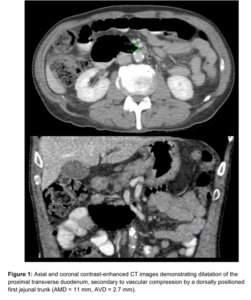

The paper of Shin[3] reports on a quite similar peculiar topographic constellation:

Image from Shin[3] – duodenal compression by the jejunal vein

According to my remarks on the paper from Yetişir [1] these authors describe the compression of the duodenum by the jejunal vein. The similarity to the case of Yetişir [1] is obvious. It would be interesting to know whether the left renal vein was compressed as well, but this was not mentioned in any of the case reports.